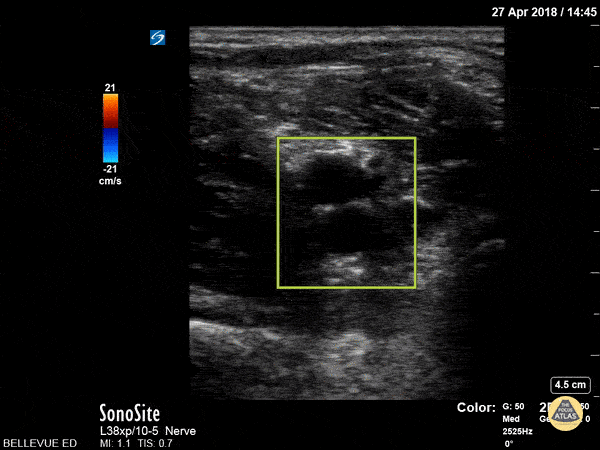

Vascular - Popliteal Vasculature - Doppler

In this clip the color doppler helps to differentiate the popliteal artery (deep, red, pulsatile) from the popliteal vein (no color, superficial). Hannah Kopinksi and Dr. Lindsay Davis - NYU Emergency Medicine